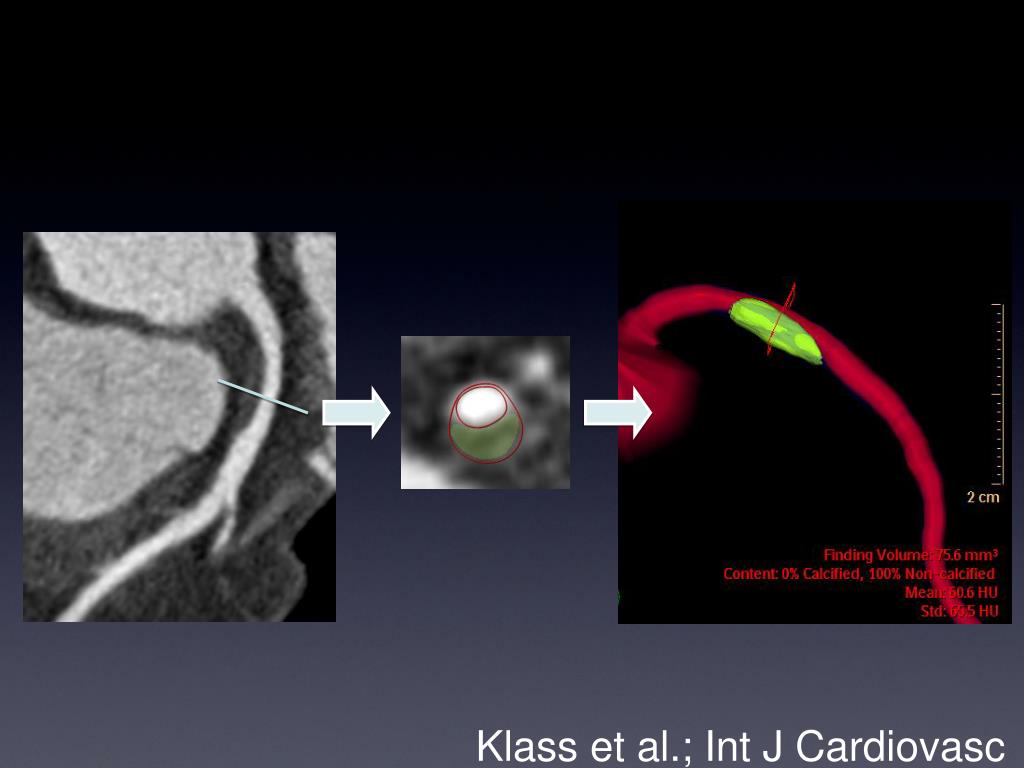

14. Klass et al.; Int J Cardiovasc Imaging 2010